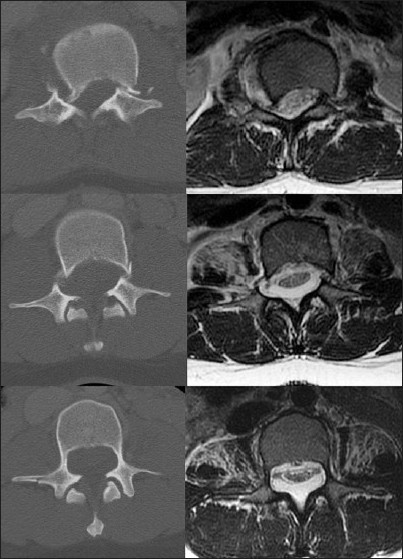

We present a case of a 20-year-old female who was an unrestrained back seat passenger in a motor vehicle collision. She denied any history of back pain, leg pain, weakness, numbness, or bowel / bladder dysfunction. She denied any history of prior surgeries. The patient presented to the ER with severe back pain and an inability to move her legs. Initial examination revealed bilateral lower extremity plegia, an L1 sensory level, and an absent rectal tone, indicating complete spinal injury. The CT scan revealed an L1 burst fracture with subluxation and bilateral pedicle fractures at L1 and L2 [Figure 1] and [Figure 2]. The patient was noted to have asymmetrically and atypically thin pedicles at these levels [Figure 2]. We suspected the presence of intraspinal pathology as the cause of the thin pedicles. Subsequent advanced imaging with MRI revealed the presence of an extradural meningeal cyst [Figure 1] and [Figure 2]. | Figure 1: (Left) sagittal T2 MRI showing fracture subluxation at L1 and the anterior displacement of the neural elements, arrow points to the dorsally located extradural meningeal cyst; (right) sagittal CT revealing the burst fracture with subluxation at L1

| Figure 2: (Top) axial CT and T2 MRI at the level of L1 showing bilateral pedicle fractures and subluxation associated with canal compromise. (Middle) axial CT and T2 MRI at the level of L2 showing bilateral pedicle fractures and a dorsally located extradural meningeal cyst. (Bottom) axial CT and T2 MRI at the level of L3 showing aberrantly thin pedicles, anterior displacement of the neural elements, and dorsally located extradural meningeal cyst

Click here to view |